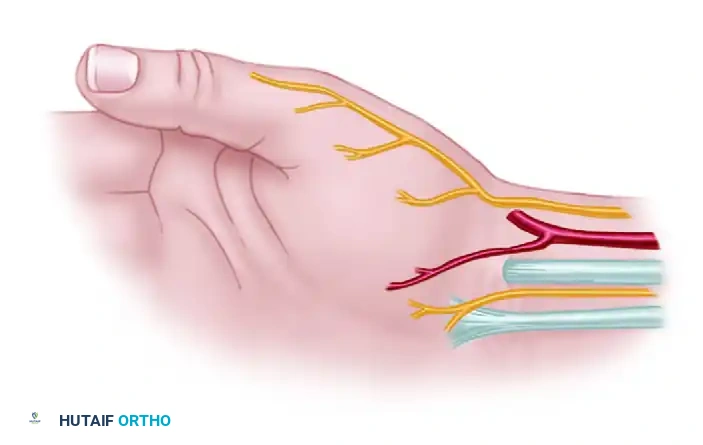

- Neurovascular Protection: Meticulous superficial dissection is critical. Three specific structures must be identified and protected:

- The superficial branch of the radial nerve (SBRN).

- The superficial branch of the radial artery.

- Palmar cutaneous sensory branches, particularly from the median nerve.

Figure: Incision for exposure, highlighting the superficial branch of the radial nerve and palmar branch of the median nerve.